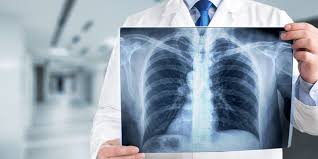

Der Raum zwischen den beiden Lungen Mediastinum ist zur Gegenseite verschoben Mediastinalverschiebung und das Zwerchfell steht auf der betroffenen Seite tiefer. Schneller Herzschlag Tachykardie Starke Schmerzen in der Brust oder Schulter. Symptome einer kollabierten Lunge aufgrund von Atelektase.

In den zu großen Blasen staut sich die Atemluft und die Ausatmung ist behindert. Die Symptome der perforierten Lunge hängen von der Menge der in die Lunge eintretenden Luft und dem Schweregrad der Perforation ab sowie davon ob eine zugrunde liegende Störung vorliegt die sie verursacht. Übersicht über die typischen Symptome Atemnot. Neben Brustschmerzen deuten normalerweise vor allem Atemnot und Atembeschwerden auf einen Lungenriss hin. Die angesammelte Luft im Pleuraraum die die Aufdehnung der Lunge behindert führt zu einer erschwerten Atmung. Eng an der Brust. Symptome einer kollabierten Lunge aufgrund von Atelektase. Dieser Kollaps kann auch Druck auf das Herz ausuben und andere Symptome verursachen. Strömt immer mehr Luft in den Pleuraraum kann sich der dadurch entstehende Überdruck auf das Herz und die umliegenden Gefäße auswirken.